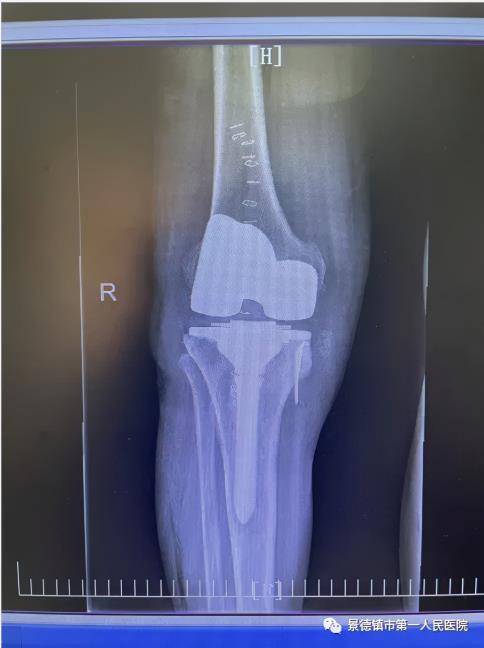

經(jīng)過屢次術(shù)前研討,袁志峰與手術(shù)隊伍醫(yī)生劉會文一同研討出手術(shù)計劃。行外表膝關(guān)節(jié)置換術(shù),盡快的保留患者更多的骨量,為20年乃至30年之后面對的再次置換供應(yīng)一個豐富的骨量貯備。并借用現(xiàn)在醫(yī)療行業(yè)最新的3D數(shù)字打印技巧,精確進行截骨和假體安頓,有效以免術(shù)后患者兩側(cè)因軟組織不平衡而導致的力線偏移,假體就愈加安穩(wěn),應(yīng)用的壽命愈加長。

8月23日,是程小華“重獲新生”的日子,1個半小時的手術(shù)流程,在程小華家人心里像過了一個時代如此長。當?shù)孟な中g(shù)十分順利后,他的家人心里好像放下一起大石。此段期間,骨二科的醫(yī)護職員時常在程小華的病房引導他復(fù)健,9月17日入院時,程小華已然能夠像常態(tài)人通常行走,他仍舊須要努力進行痊愈錘煉,逐漸修復(fù)大腿肌肉。